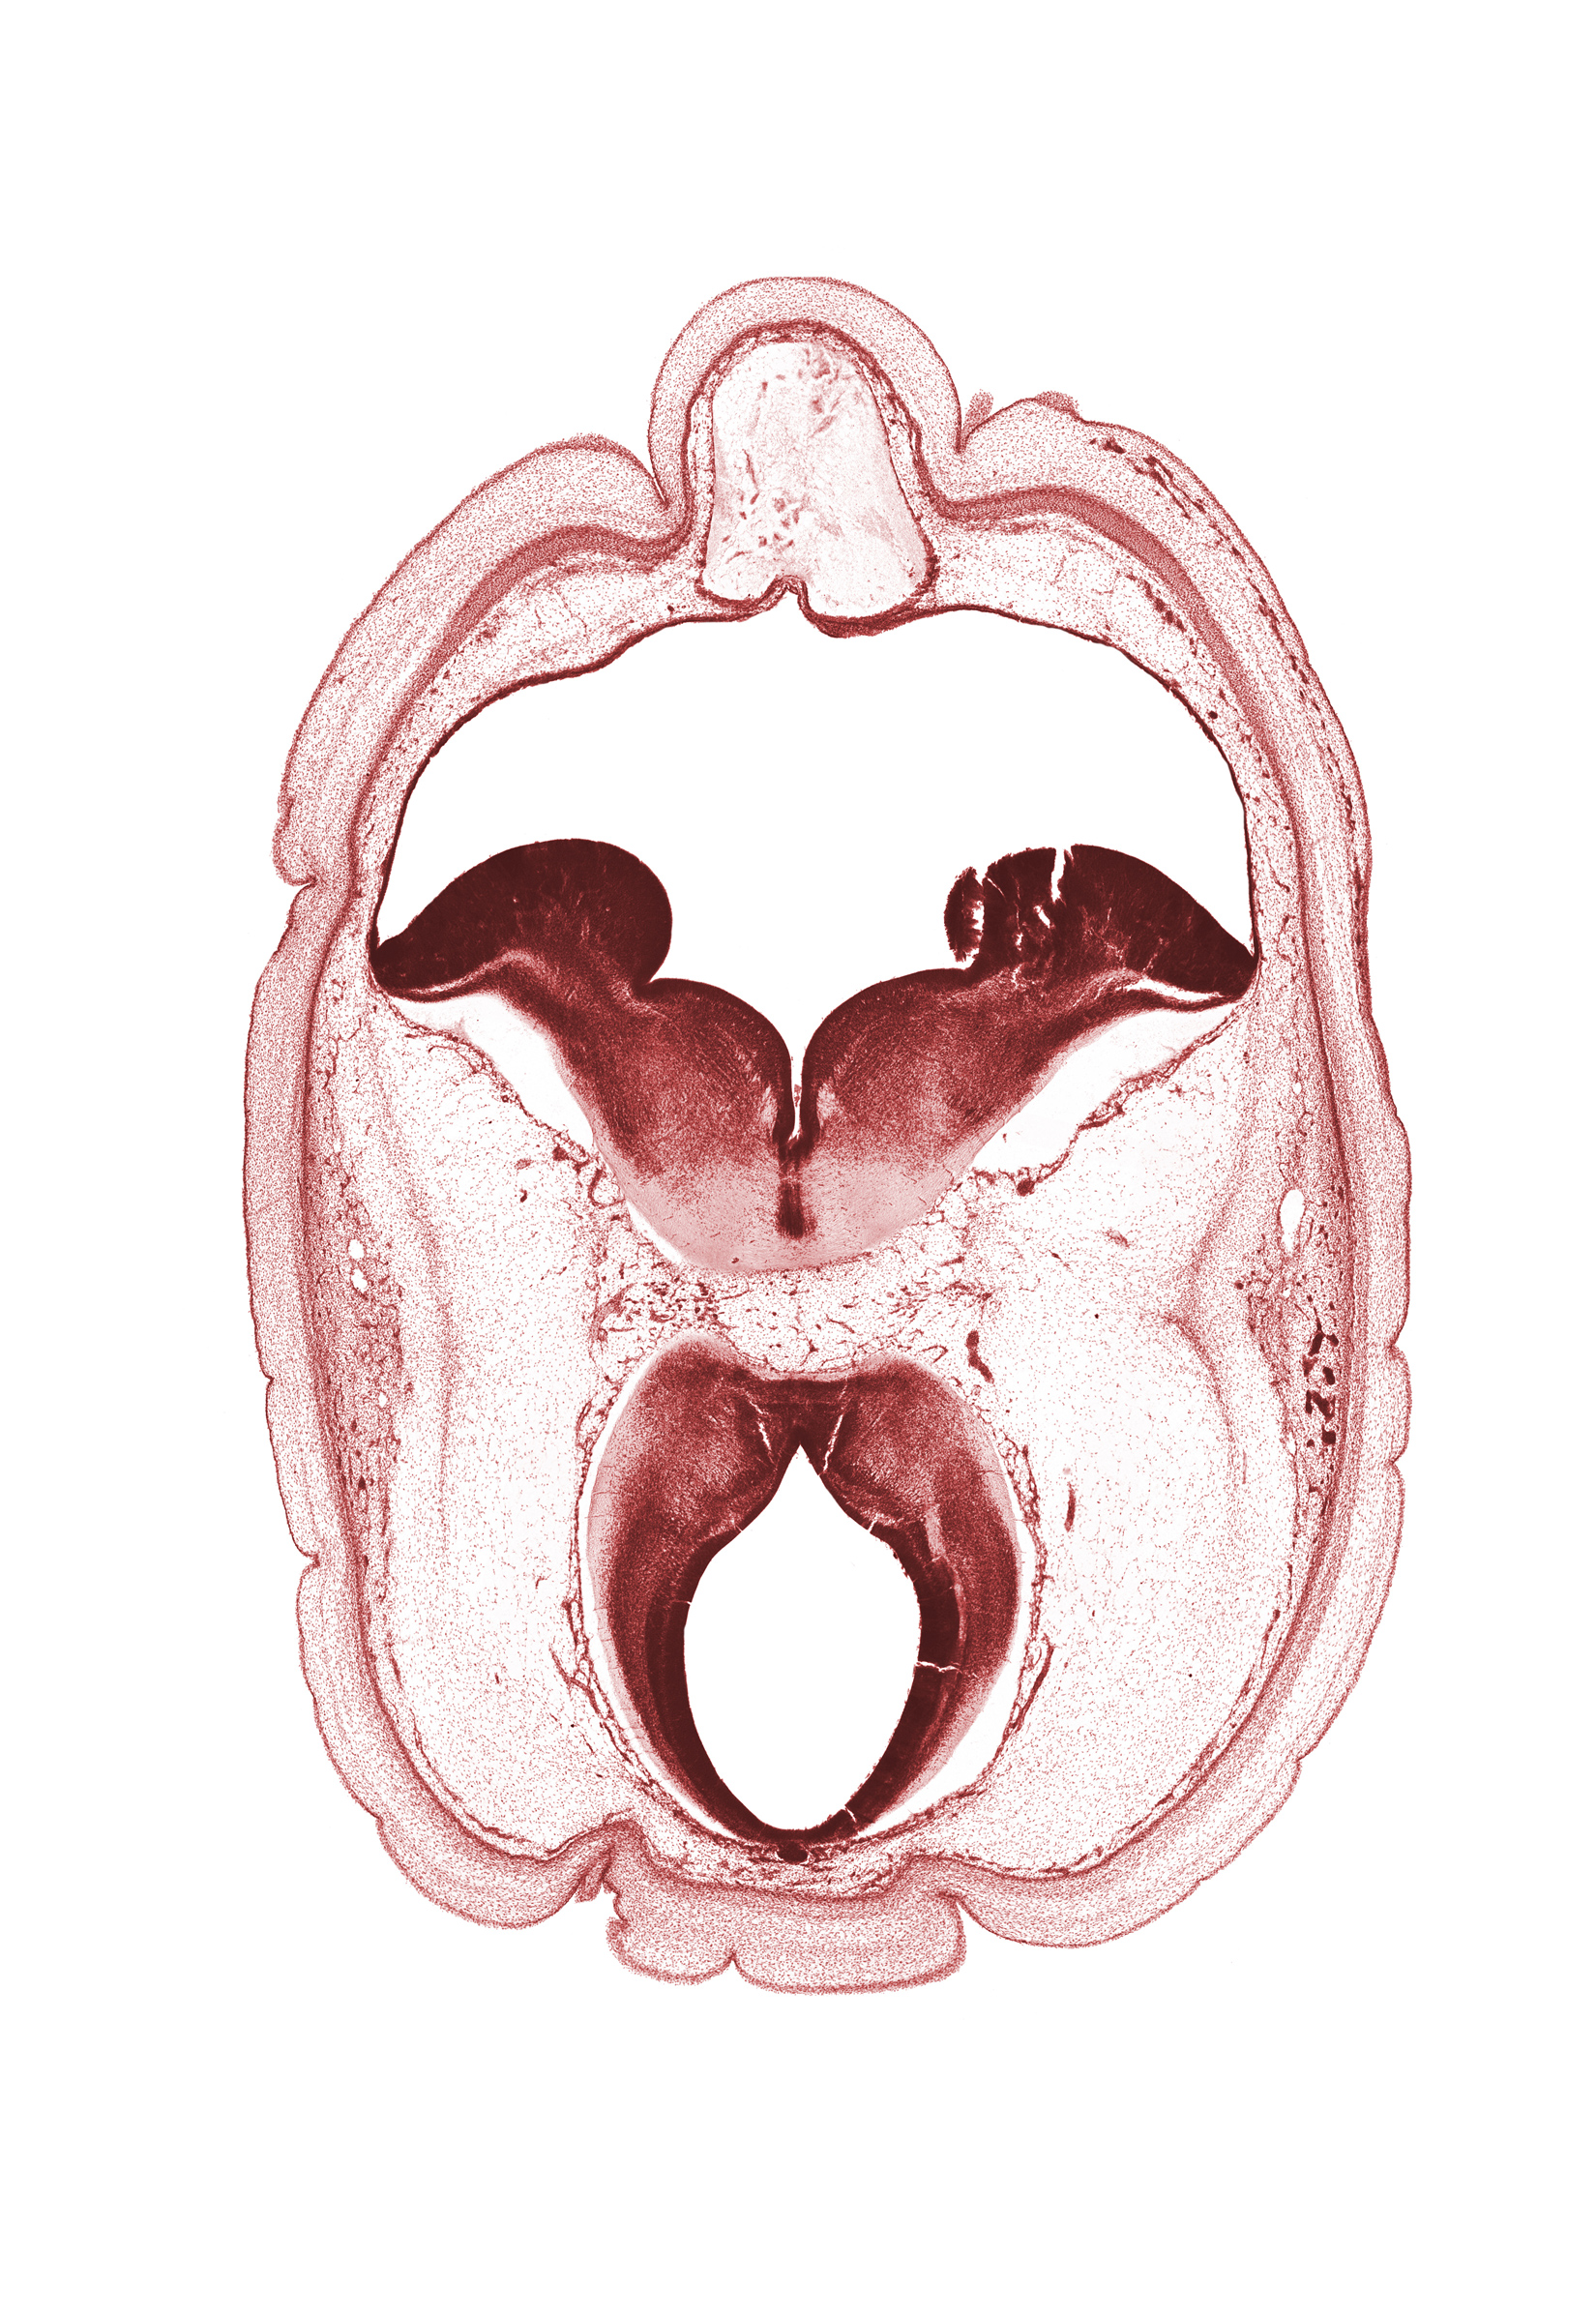

0 μm

Carnegie Embryo #4090 | Location: 4-6

Keywords: artifact fracture(s), artifact space(s), cephalic part of dural band for tentorium cerebelli, cerebral aqueduct (mesocoele), osteogenic layer, pons region (metencephalon), region of mesencephalic (cephalic) flexure, rhombencoel (fourth ventricle), root of oculomotor nerve (CN III), subarachnoid space, superficial vascular plexus

Source: The Virtual Human Embryo.